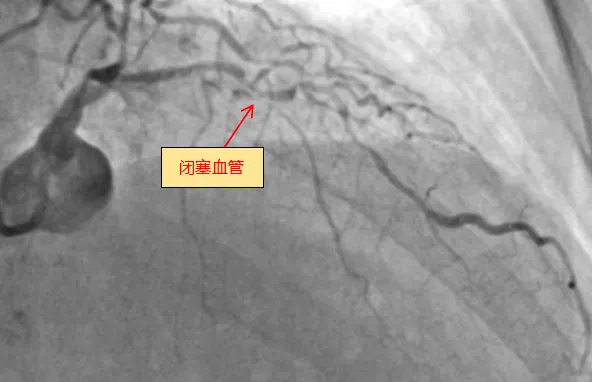

6月13日,皇冠足球投注网 (简称皇冠足球网 )心血管内科团队成功完成全新ROTAPRO™旋磨介入治疗系统上市后在广西的首次应用,为一名复杂高危严重钙化患者进行了精准冠脉介入治疗,顺利开通闭塞的冠脉血管并完成支架植入。71岁的梁阿姨(化名)去年外院冠脉造影诊断为冠心病,三支血管严重狭窄,于右冠植入一枚支架,前降支严重钙化病变尝试开通失败。近几个月来,她反复出现胸痛症状...